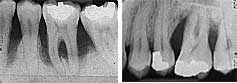

Alt ve üst büyükazı bölgelerinde yaygın kemik erimelerinin rontgen görüntüleri

Periodontitiste çene kemiğinin erimesiyle birlikte, diş kökünün çene kemiği içinde kalan bölümü azalır. Bir sonraki aşama, dişlerin sallanmaya başlaması ve kaybedilmesidir.